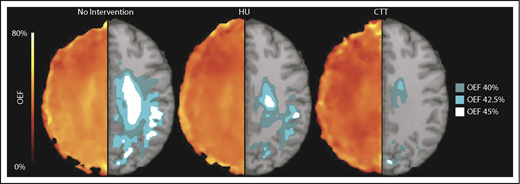

We identified that the region of greatest OEF was located in the deep white matter (Figure 2), where CBF is found to be at a nadir, consistent with prior reports.33,36 To determine the effect of HU on regional OEF, as an indicator of tissue at heightened risk for ischemia, we thresholded individual OEF maps to measure white matter volumes with OEF values greater than 40%, 42.5%, and 45%. The cohort receiving HU had a lower percentage white matter volume with OEF values greater than 40% (P = .025), 42.5% (P = .034), and 45% (P = .052) when compared with the cohort not receiving disease-modifying therapy. However, the HU cohort had a higher percentage white matter volume with OEF values greater than 40% (P = .018), 42.5% (P = .029), and 45% (P = .035) when compared with the CTT cohort (Table 3). We further quantified the percentage of patients within each voxel with high OEF, defined as greater than 40%, 42.5%, and 45%. Figure 3 illustrates the prevalence of patients with OEF above the 3 thresholds across the 3 cohorts. The highest prevalence of elevated OEF consistently falls within the internal border zone in all 3 cohorts, with a stepwise decrease in prevalence of regional peak OEF for the HU and CTT cohorts compared with the cohort not receiving disease-modifying therapy.

HU decreases the volume of brain tissue with elevated OEF in the border zone. The average white matter OEF map for each cohort was thresholded at 40% (dark teal), 42.5% (light teal), and 45% (white) OEF to identify the brain regions with peak oxygen metabolic stress, as a potential index of elevated stroke risk. The figure shows the average OEF map for each cohort (left), paired with the thresholded regions overlaid on a T1 atlas (right). There is a decrease in thresholded brain tissue in the cohort treated with HU when compared with those not receiving disease-modifying therapy across all thresholds, but the cohort receiving CTT has a significantly lower volume of at risk tissue compared with the HU cohort.